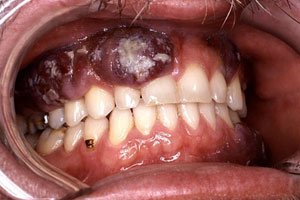

Суть метода заключается в воздействии на опухолевый очаг жидким азотом, что вызывает снижение местной температуры и полной заморозки патологических тканей. Процедура, которая проводится в амбулаторных условиях, не влечет за собой образования косметических дефектов и прочих осложнений, эффективно устраняет саркомы небольшого размера. Часто применяется в случае сарком Капоши, развивающихся на слизистой полости рта или коже лица.